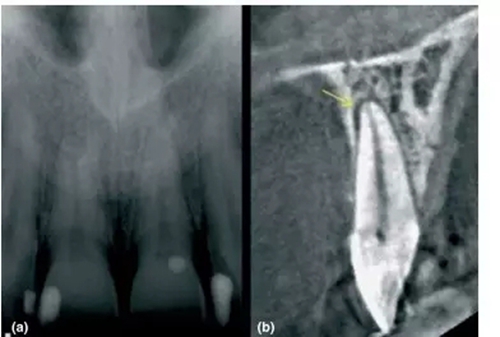

1,根尖周炎的探測

a- 11和21根尖影像無異常,但患者主訴該區(qū)有間歇的鈍痛

b-CBCT顯示21腭側(cè)有透射影,根管治療后患者癥狀消失

前文中已經(jīng)討論了能顯示在傳統(tǒng)X片上根尖周暗影,其范圍一定侵犯到皮質(zhì)骨。然而CBCT卻能精準探測只局限于松質(zhì)骨中的病損,讓臨床醫(yī)生能早診斷、早處理,提高現(xiàn)代牙體牙髓治療的成功率。